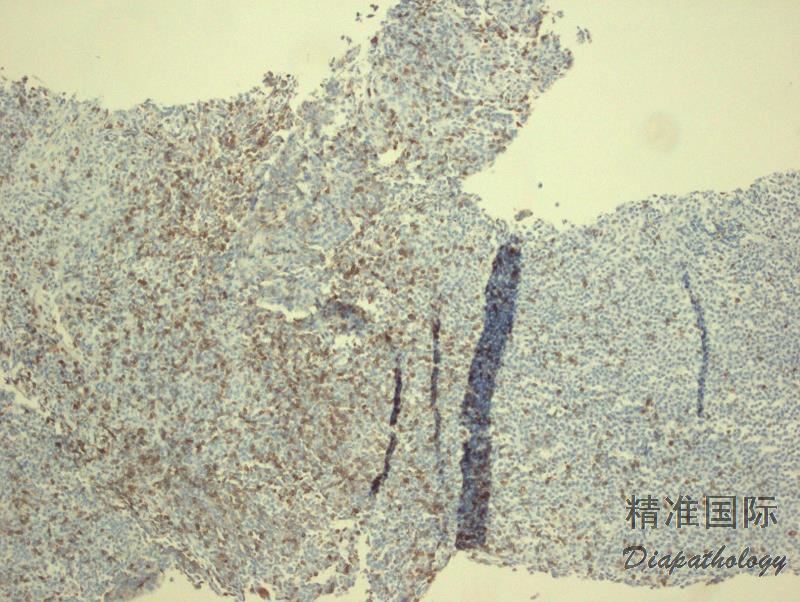

- 外周血可见循环肿瘤细胞和红细胞成钱串样重叠;骨髓几乎总是受侵犯,非小梁旁或小梁旁, 间质或弥漫侵润;淋巴结受侵以副皮质区为明显,可累及整个淋巴结。肿瘤细胞由小淋巴细胞、浆淋巴细胞和浆细胞谱系组成,可见 Dutcher 或 Russell 小体。肥大细胞数增加。

- 免疫组化和流式细胞 CD20 等 B 细胞抗原阳性,轻链染色或原位杂交揭示单克隆浆淋巴细胞或浆细胞。